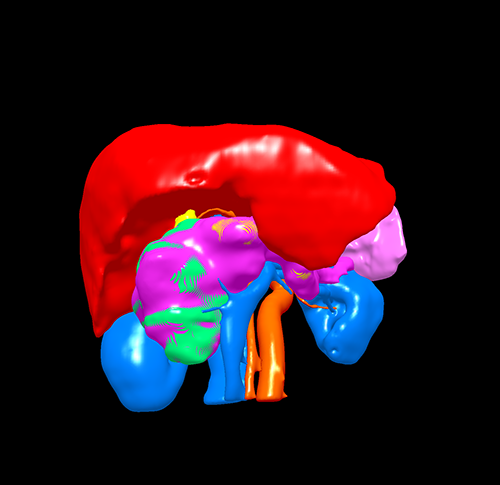

三维重建

胰头囊腺瘤---胰十二指肠切除